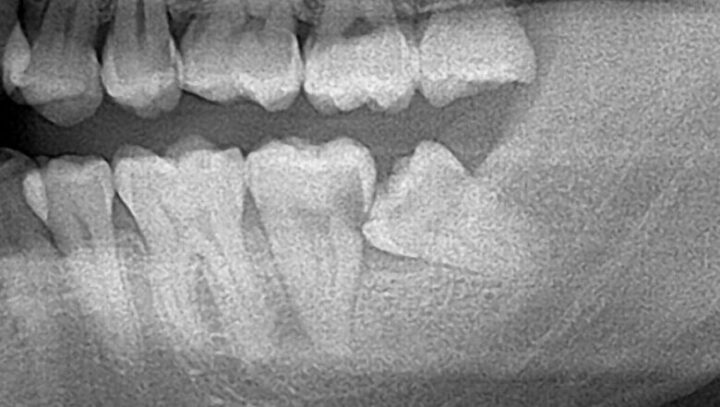

まずは、歯科受診時に歯周病や虫歯の診断の為の大きなパノラマレントゲン写真を撮る機会があると思います。

その際に親知らずの有無がわかりますので、担当の先生に親知らずの状態についても伺う事をお勧めします。

そのため歯科医師は、通常のレントゲンである程度の歯と神経との距離を確認し、レントゲンで見て歯と神経が近い場合や、距離関係がわかりづらい場合はCTを撮影し正確な位置を確認することがあります。